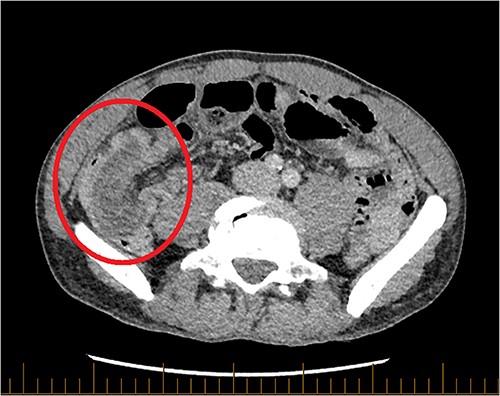

Computer-tomography (CT) demonstrated two points of synchronous intussusception. First, a relatively long segment ileocolic intussusception (Fig. 1) with dilated distal ileum containing faeculent matter, indicative of bowel obstruction. Second, a short segment small bowel intussusception involving jejunal loops (Fig. 2).

Axial CT of the abdomen and pelvis with portal venous contrast. Long segment of ileocolic intussusception shown (red circle).